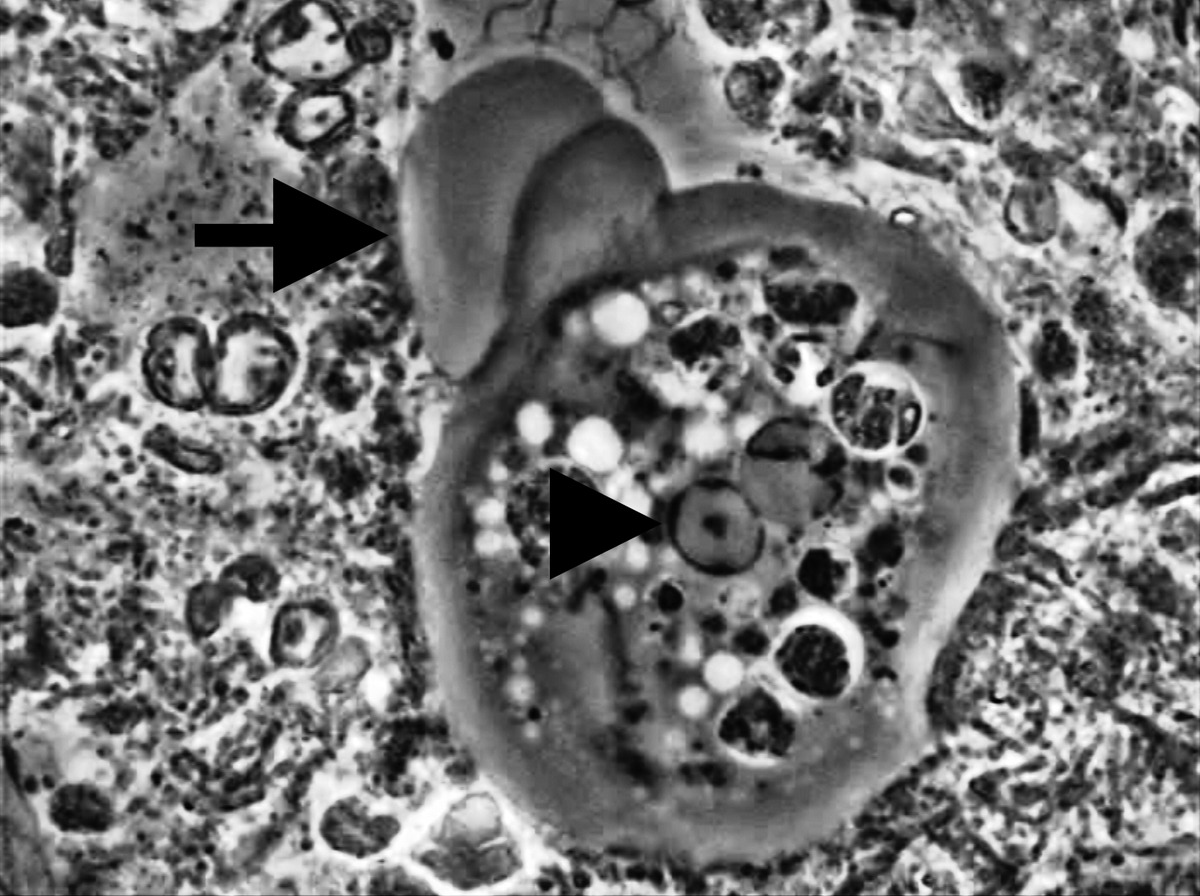

Il ruolo di Entamoeba gingivalis nella Parodontite